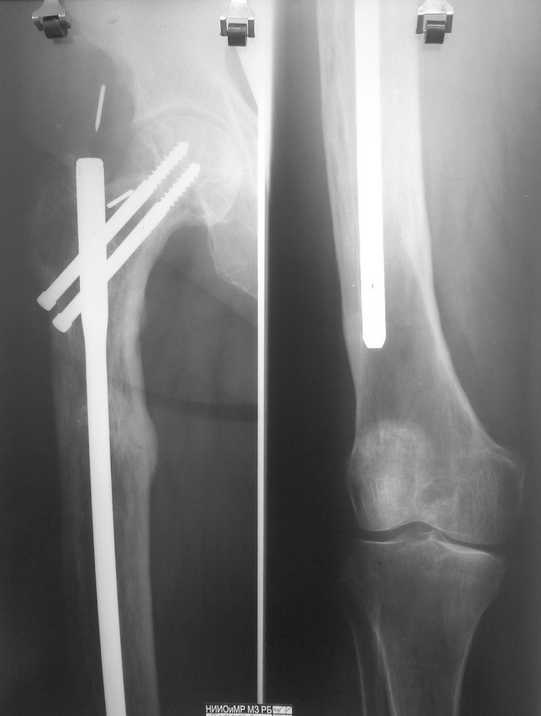

болезнь Педжета

Год назад посылал сообщение о патологическом переломе на фоне болезни Педжета. Вот, в итоге, все зажило. Сообщение посылаю так, для ознакомления, может кому-то будет интересно. Всех с Рождеством!